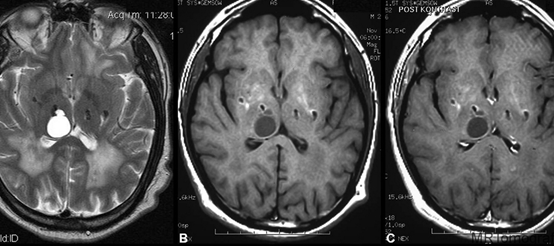

MRG tetkikleri diğer görüntüleme yöntemleri ile iyi değerlendirilemeyen yumuşak doku hastalıklarında son derece yardımcı bir yöntemdir. Özellikle beyin-omurilik, boyunla ilgili hastalıklarda ve kas-iskelet sitemi ile ilişkili hastalıklarda kullanılan en gelişmiş kesitsel görüntüleme yöntemidir. Ayrıca karaciğer, pankreas gibi karın içi organlarda, kalp ve damar hastalıklarında da güvenle kullanılır.